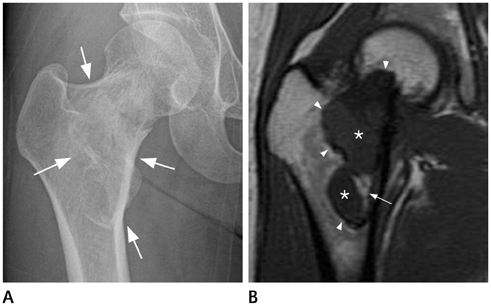

Systematic Approach of Sclerotic Bone Lesions Basis on Imaging Findings

- Sclerotic bone lesions are common, but there are diverse groups of tumors and non-tumorous lesions. Although plain radiograph and computed tomography can reveal important characteristics of these lesions, diagnosis is often challenging for radiologists. A systematic approach and familiarity with the imaging features of various sclerotic bone lesions may be greatly helpful for eliminating in the differential diagnosis. This review describes the systematic approach to diagnosing sclerotic bone lesions based on imaging findings.